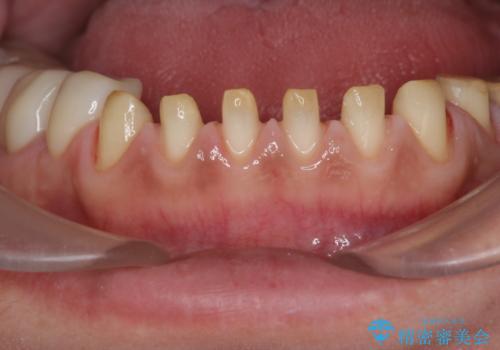

歯ぎしりですり減った 前歯の見た目を回復したい

- 歯ぎしり・嘔吐症により歯がすり減ってしまい、色調・見た目を改善したいと来院されました。

神経を温存したまま仮歯に置き換え、噛み合わせの安定を確認したのちに すり減りに強いジルコニアクラウンで最終的な仕上げを行います。